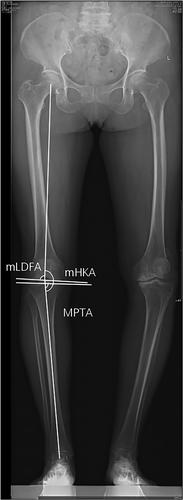

This retrospective cohort study analysed 244 patients who underwent nonrobotic-assisted medial fixed-bearing UKA between 2015 and 2018 with a minimum 2-year follow-up. Patients were categorised into prearthritic and nonprearthritic alignment groups based on the difference between their postoperative alignment and prearthritic hip-knee-ankle angle. Postoperative outcomes, including the Forgotten Joint Score (FJS-12), Oxford Knee Score (OKS) and Western Ontario and McMaster Universities Osteoarthritis Index (WOMAC), Knee Injury and Osteoarthritis Outcome Score (KOOS), Oxford Knee Score (OKS) and University of California Los Angeles (UCLA) activity score were compared between the groups. Additional analysis was performed in a subgroup of patients with constitutional varus alignment (CPAK types I, IV and VII). Multivariable logistic regression was used to identify predictors of achieving a forgotten joint.